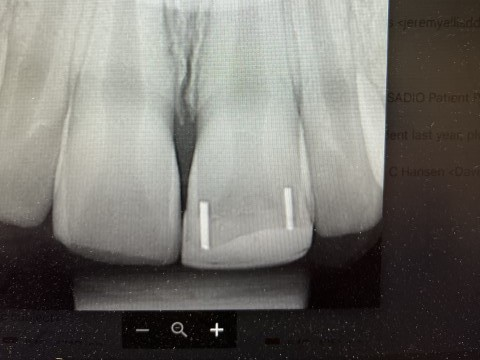

DentXpinTM repair.

2